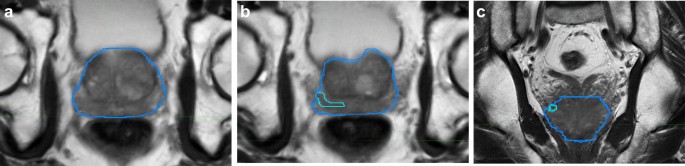

My urologist performs a transrectal ultrasound to establish medical necessity to proceed with the prostate biopsy. MRITRUS Fusion Biopsy First an advanced MRI prostate image is obtained annotated and recorded by. In most cases only a few biopsy cores are needed such is the accuracy of the procedure.

MRI-Guided Biopsy Using advanced MRI images of a suspected tumortissue Dr. The probe is of the size of a finger. An MRI of the prostate followed by a targeted 3D MRIUS Fusion Biopsy can significantly increase detection grading and staging of disease.

Therefore for easy payment and in most cases use the usual three codes for a prostatic needle biopsy. The MRIultrasound fusion biopsy begins with a prostate MRI performed in a 3T MRI. Diagnostic MRI and the biopsy can be scheduled on separate days.

The MRI fusion prostate biopsy is a two-step process. MRI fusion prostate biopsy is performed by inserting an ultrasound probe. As there is no specific CPT code to report the MRI-TRUS fusion biopsy procedure currently urologists can only report the three or two codes for a standard TRUS guided biopsy based on Medicare or commercial insurers guidance.